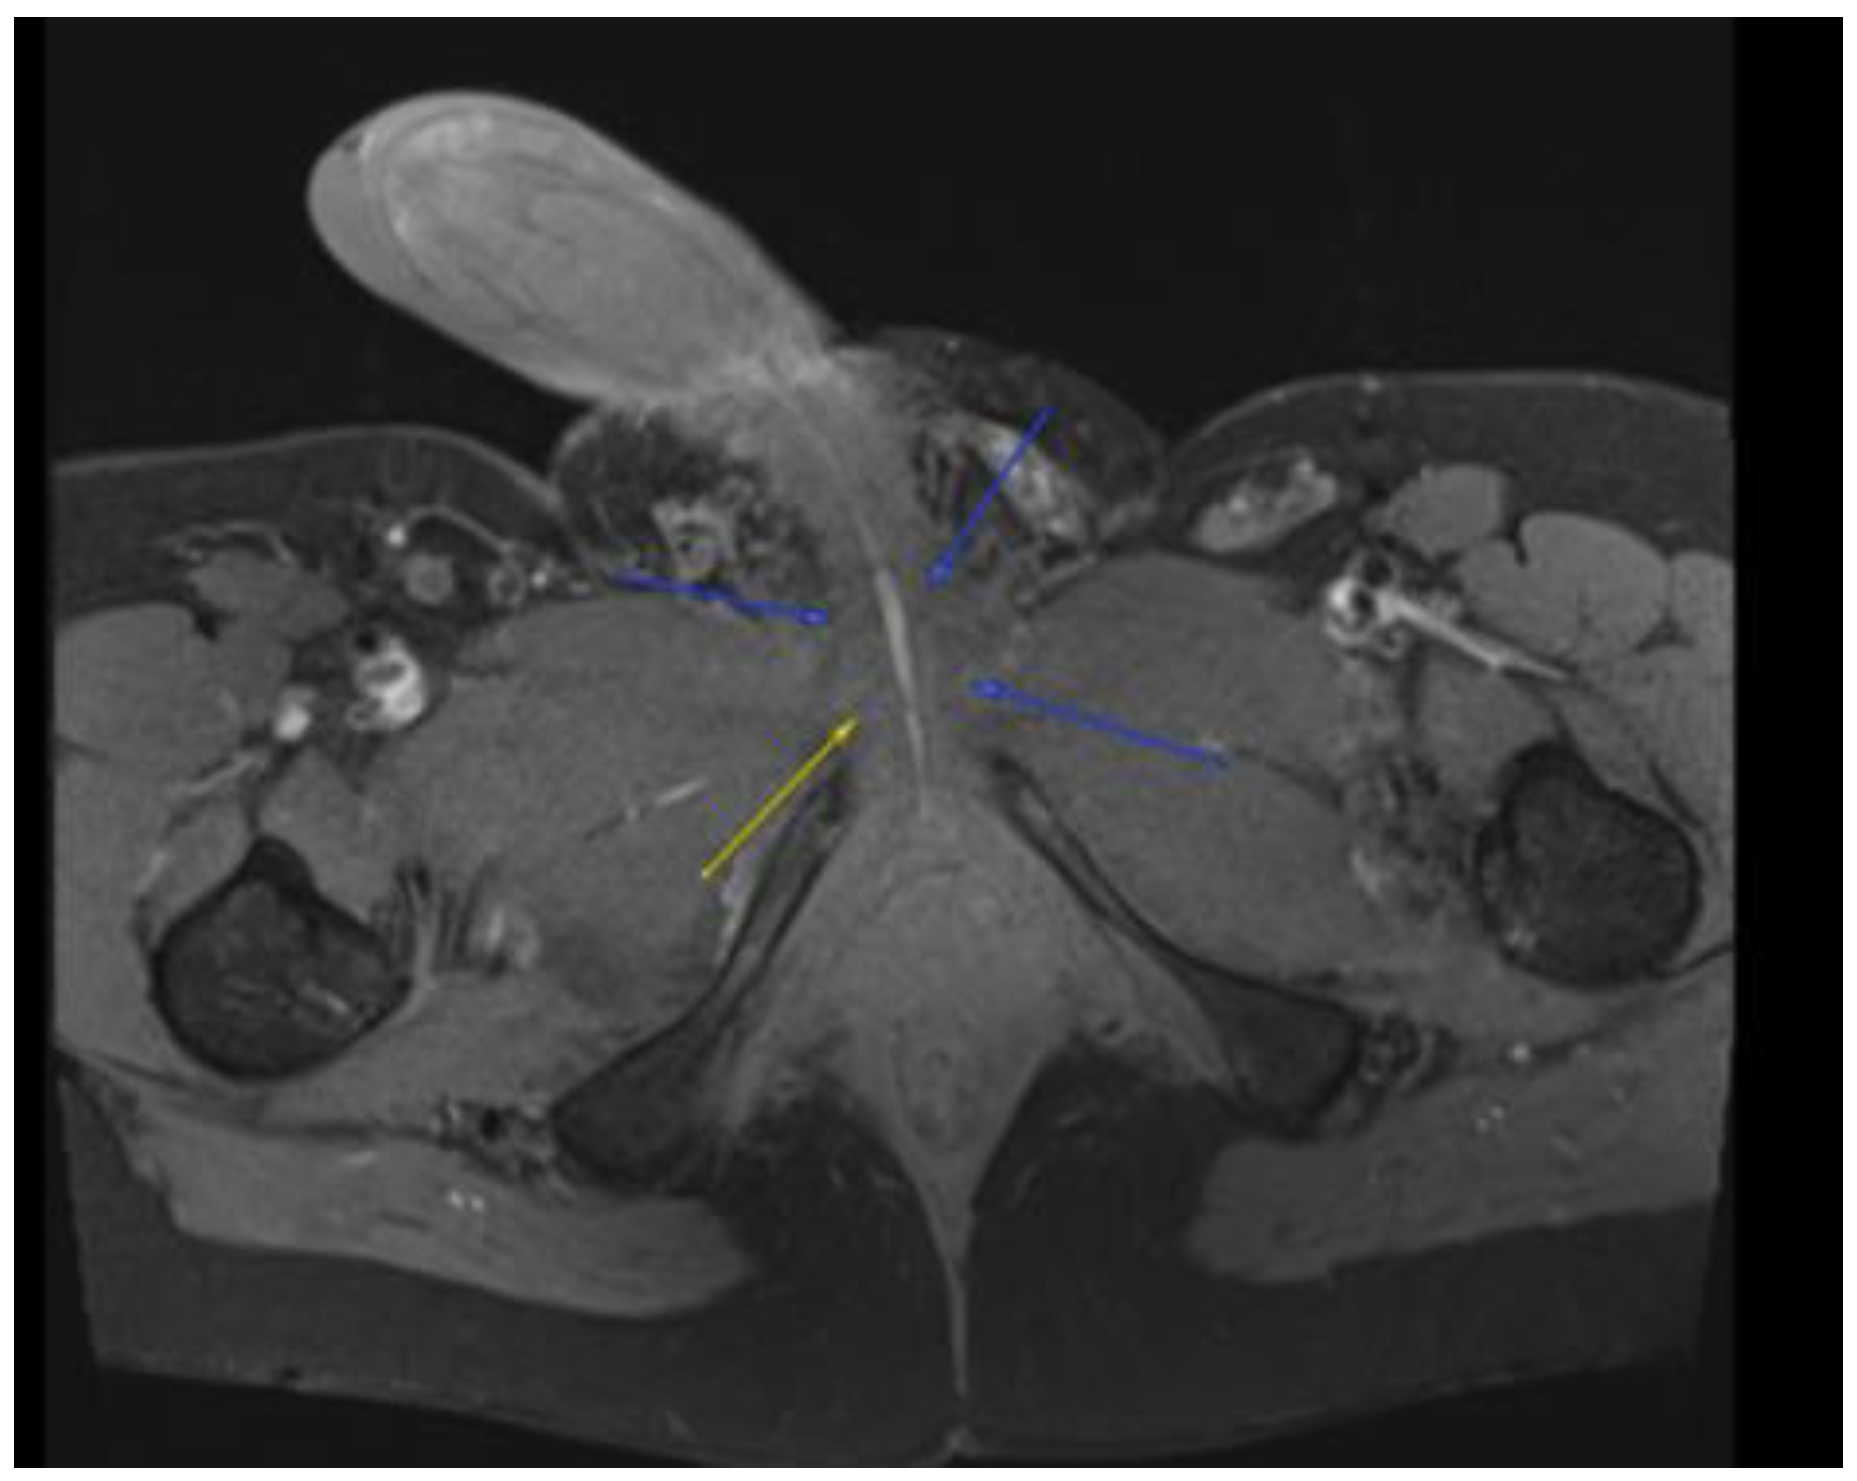

Figure 5.

MRI in the axial view T1 TSE FS pre-showing 22 × 30 mm bilateral inguinal lymph node.